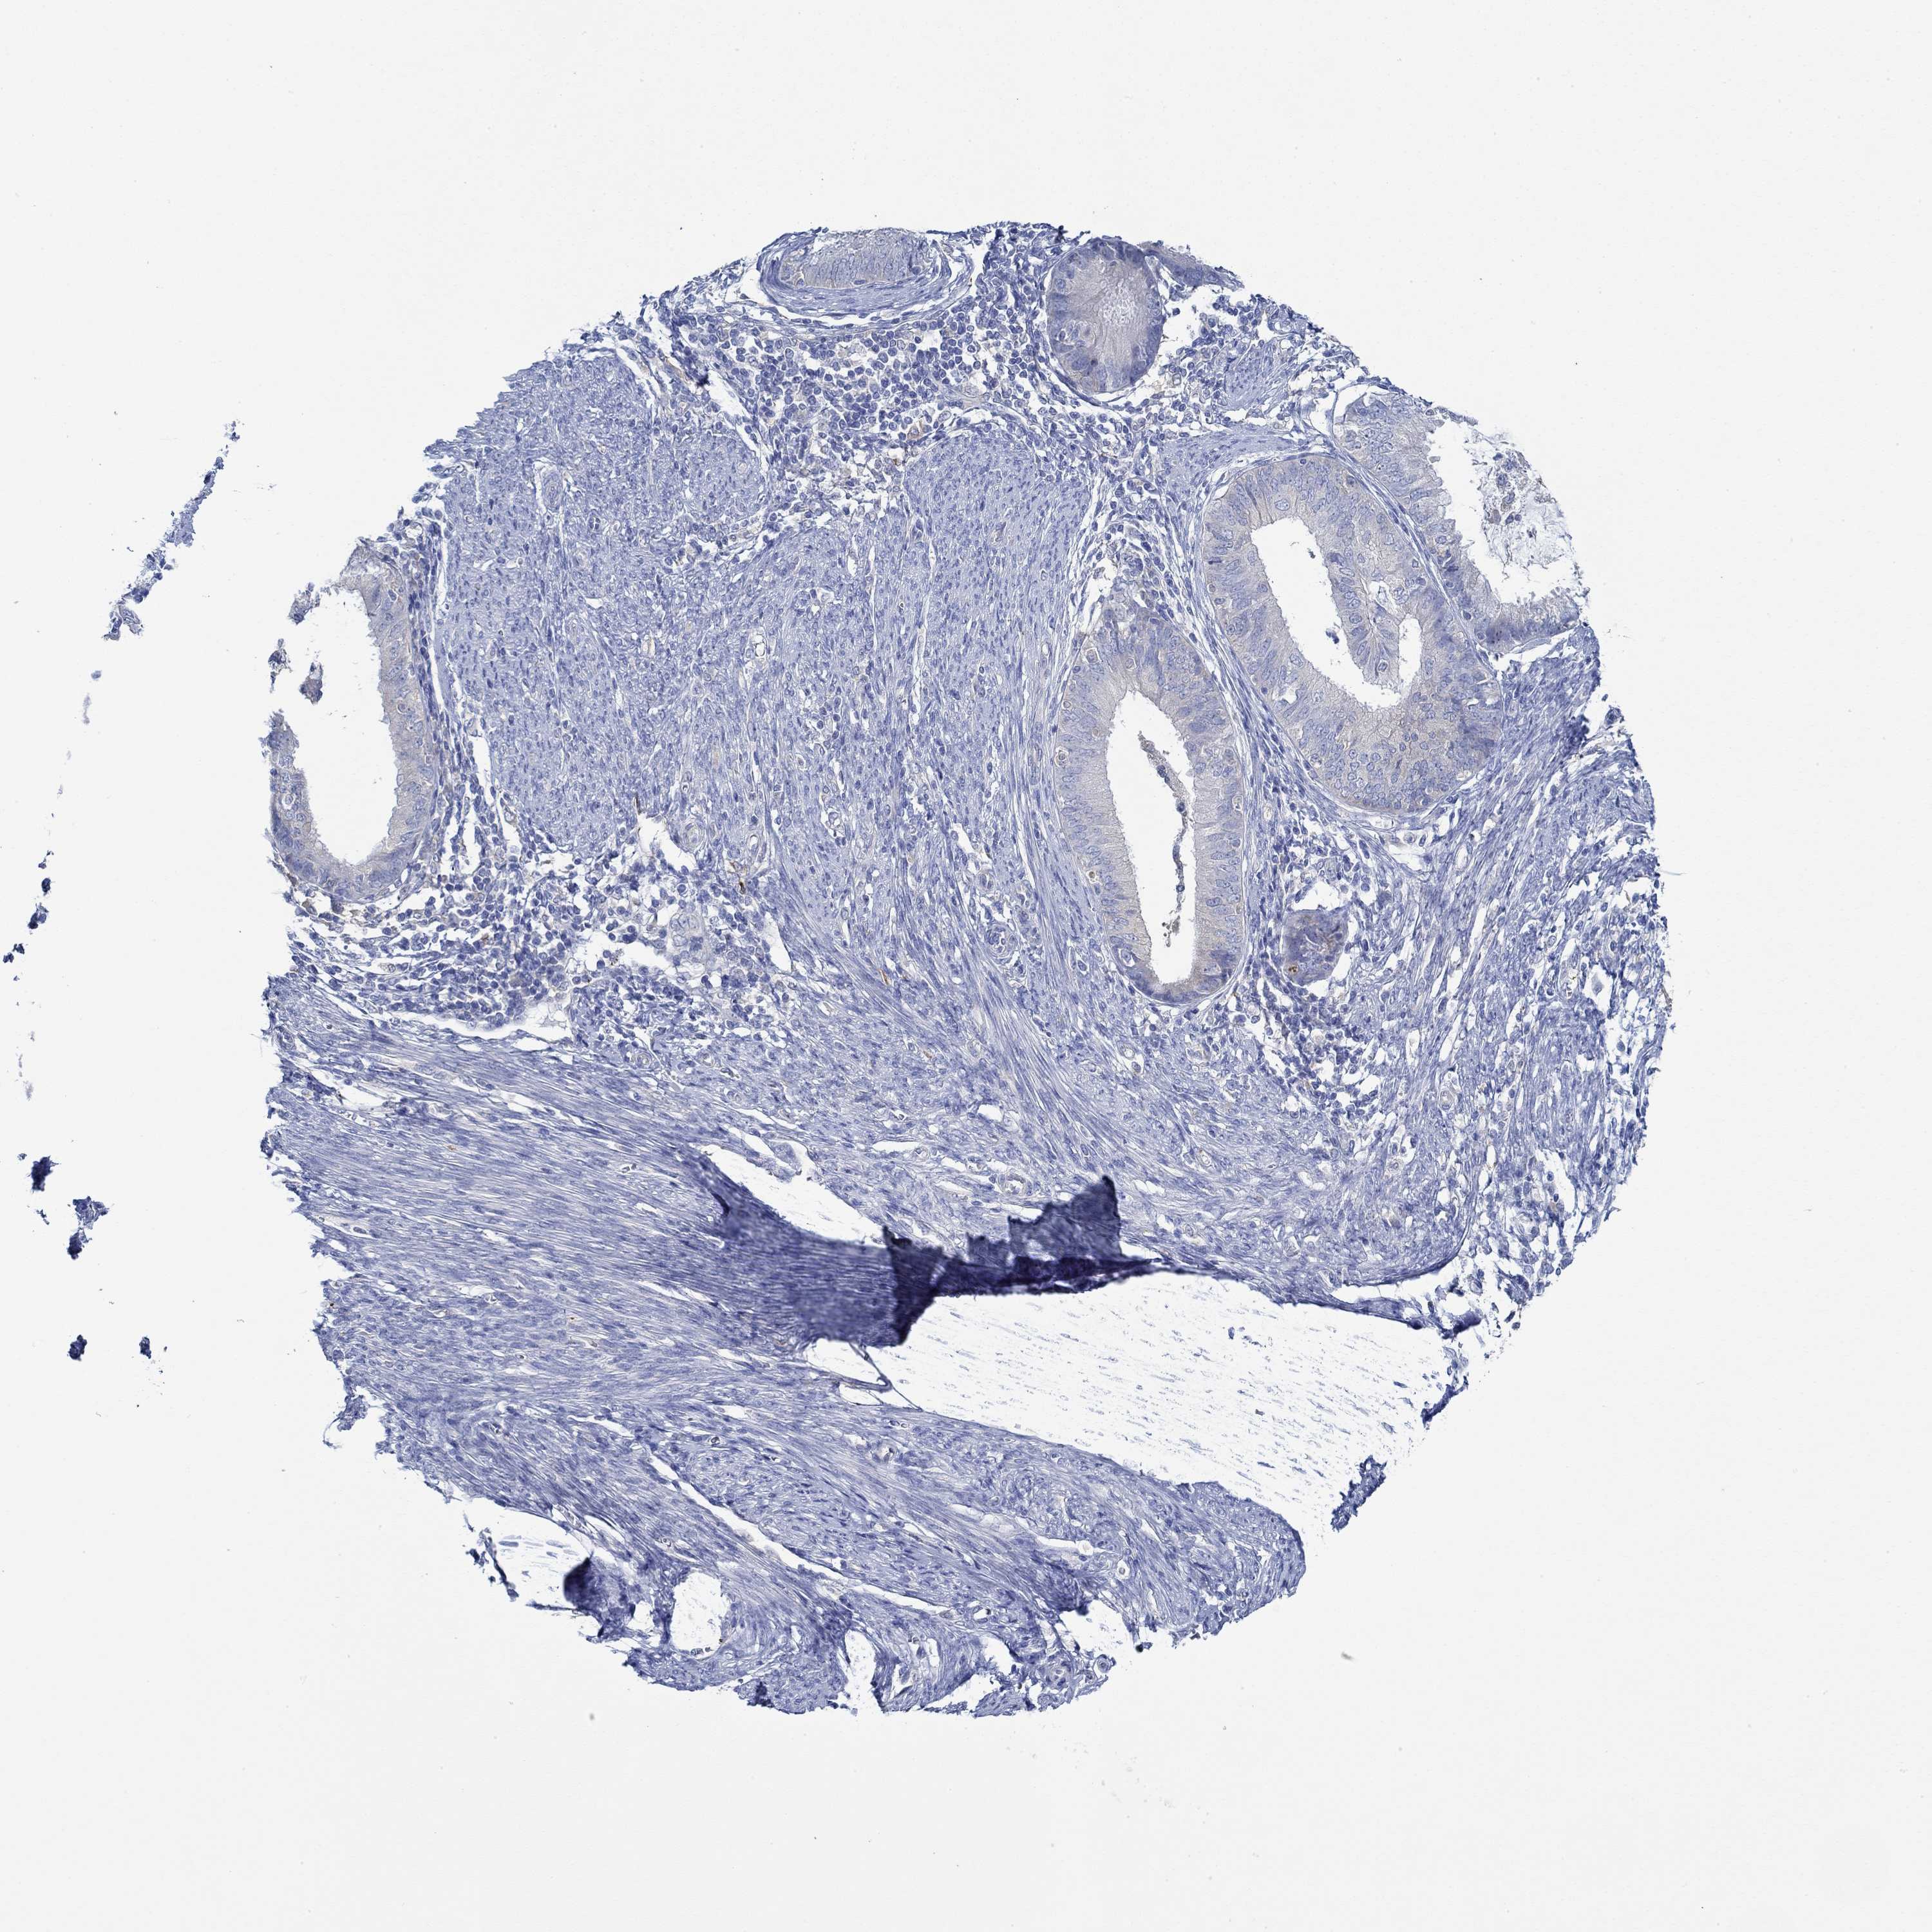

ENDOMETRIAL CANCER - Protein expressioni

A mouse-over function shows sample information and annotation data. Click on an image to view it in a full screen mode. Samples can be filtered based on level of antibody staining by selecting one or several of the following categories: high, medium, low and not detected. The assay and annotation is described here.

Note that samples used for immunohistochemistry by the Human Protein Atlas do not correspond to samples in the TCGA dataset.

Antibody stainingi

Antibody staining in the annotated cell types in the current human tissue is reported as not detected, low, medium, or high, based on conventional immunohistochemistry profiling in selected tissues. This score is based on the combination of the staining intensity and fraction of stained cells.

Each image is clickable and will lead to virtual microscopy that enables deeper exploration of all samples and also displays staining intensity scores, fraction scores and subcellular localization as well as patient and tissue information for each sample.

Antibody HPA067508

Antibody CAB080514

Antibody CAB080517

Staining

High

Medium

Low

Not detected

Intensity

Strong

Moderate

Weak

Negative

Quantity

>75%

75%-25%

<25%

None

Location

Nuclear

Cytoplasmic/membranous

Cytoplasmic/membranous,nuclear

Adenocarcinoma, NOS

Adenocarcinoma, metastatic, NOS